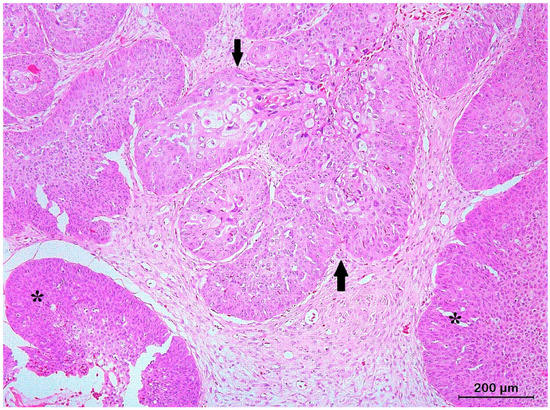

3.2. Squamous Cell Carcinoma and Its Histological Variants

3.3. Basal Cell Carcinoma and Its Histological Variants